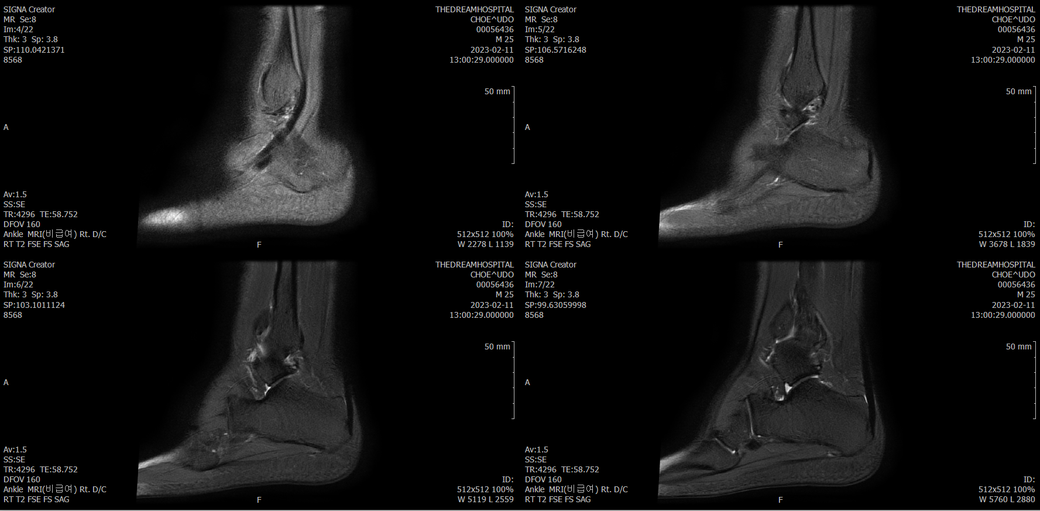

오른발목 mri 전체사진입니다. 제가 병원을 갈수없는상황인지라.... 봐주시면 감사하겠습니다.

엑스레이에서는 문제가 없다고 하여 오른발목 mri촬영했습니다.